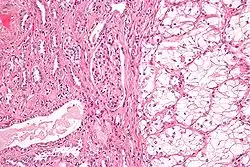

![]() صورة مجهرية تظهر أكثر أنواع سرطان الكلية شيوعا وهو (سرطانة الخلايا الكلوية ذو الخلايا الصافية) على يمين الصورة، وكلية طبيعية على يسار الصورة، عينة من كلية مستأصلة مصبوغة بصبغة الهيماتوكسيلين، واليوزين. صورة مجهرية تظهر أكثر أنواع سرطان الكلية شيوعا وهو (سرطانة الخلايا الكلوية ذو الخلايا الصافية) على يمين الصورة، وكلية طبيعية على يسار الصورة، عينة من كلية مستأصلة مصبوغة بصبغة الهيماتوكسيلين، واليوزين. | |

مرضيات الأنسجة

المظهر العيني والمجهري لسرطان الخلايا الكلوية متغير للغاية. قد يظهر سرطان الخلايا الكلوية على شكل مناطق حمراء، مع نزف الأوعية الدموية، والخراجات التي تحتوي على سوائل مائية.[54] ويحتوي جسم الورم على أوعية دموية كبيرة لها جدران تتألف من خلايا سرطانية. حيث يُظهر الفحص العيني غالبا ورم أصفر متعدد الفصوص في القشرة الكلوية، ويحتوي غالبا على مناطق نخر، ونزيف، وتندب. بينما في السياق المجهري، هناك أربعة أنواع فرعية نسيجية رئيسية من سرطان الخلايا الكلوية: خلية صافية (سرطان الخلايا الكلوية التقليدي، 75٪)، وحليمي (15٪)، وكاره للون (كروموفوبيك) (5٪)، والقناة الجامعة (2٪). ويمكن ملاحظة التغيرات الساركوماتية ضمن أي نوع فرعي من سرطان الخلايا الكلوية، مصاحبة بمسار سريري أكثر عدوانية، وتوقعات مستقبلية أسوأ. تحت المجهري الضوئي، يمكن لهذه الخلايا السرطانية إظهار الحليمات، أو الأنابيب أو الأعشاش، وتكون كبيرة جدا، وغير نمطية، ومضلعة.

قد جلبت الدراسات الحديثة الانتباه إلى الارتباط الوثيق لذلك النوع من الخلايا السرطانية بشدة شراسة الحالة. وتشير بعض الدراسات إلى أن هذه الخلايا السرطانية تُراكم الجليكوجين، والدهون، ويظهر السيتوبلازم صافي، ولا تزال النوى في منتصف الخلايا، والغشاء الخلوي واضح.[55] وقد تكون بعض الخلايا أصغر، مع سيتوبلازم يوزيني، تشبه الخلايا الأنبوبية الطبيعية. وتكون السدى قليلة، ولكن بها الكثير من الأوعية الدموية. ويقوم الورم بضغط النسيج المحيط به، مما ينتج عنه محفظة كاذبة.[56]

النوع الأكثر شيوعا من الخلايا التي يظهرها سرطان الخلايا الكلوية هو الخلية الصافية، التي قد سميت بهذ الاسم بسبب ذوبان نسبة الدهون العالية الموجودة في سيتوبلازم الخلية. ويعتقد أن الخلايا الصافية هي الأقل احتمالا للانتشار، وعادة ما تستجيب بشكل أفضل للعلاج. ومع ذلك، فإن معظم الأورام تحتوي على خليط من الخلايا. ويعتقد أن المرحلة الأكثر عدوانية من سرطان الكلى هي التي تكون فيها الخلايا مختلطة؛ تحتوي على كل من خلايا صافية، وحبيبية.[57]